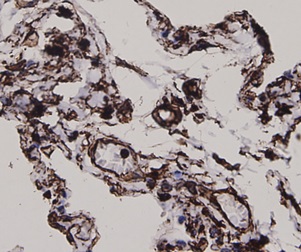

ApplicationsFlow Cytometry, Western Blot, ImmunoCytoChemistry, ImmunoHistoChemistry

- ApplicationsFlow Cytometry, Western Blot, ImmunoCytoChemistry, ImmunoHistoChemistry